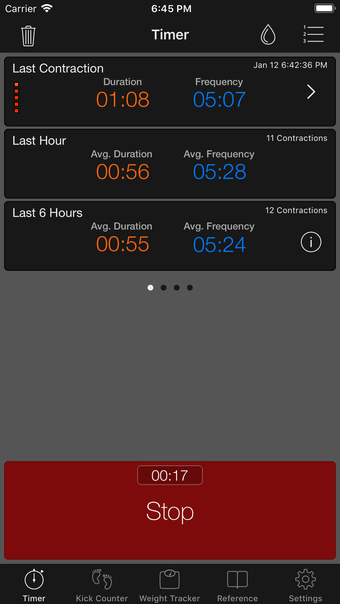

이 어플리케이션은 분만 진행 상황을 명확하게 보여주며, 현재 분만 단계, 이전 및 현재 수축의 시작 및 종료 시간을 보여줍니다. Full Term은 수동으로 각 수축을 시작하고 중지할 필요가 없으며, 어플리케이션을 재시작하더라도 분만 기록을 추적합니다.

수축 옵션 화면에서 어플리케이션이 각 수축 후 자동으로 시작되지 않도록 설정할 수 있는 옵션이 추가되었습니다.